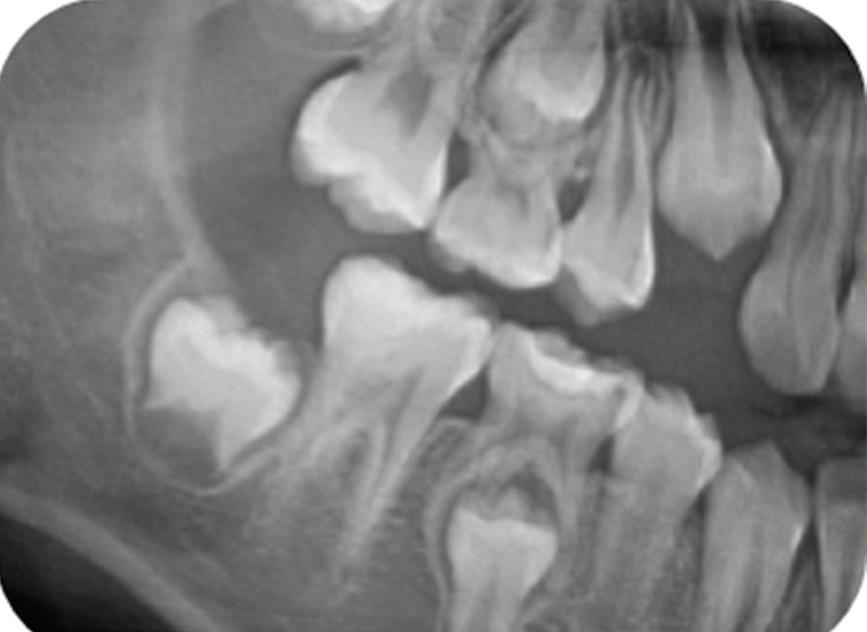

Approximately 15 months after SSC placement (49 months after PP), the patient returned with a complaint of sensitivity to cold stimuli in the treated tooth. Cold testing elicited sharp pain lasting approximately 10 seconds, but the results of the electric pulp test and percussion test were negative. Radiographic examination of the first molar showed a periapical radiolucency with a periapical index score of 3 (Fig 8).9 The tooth was diagnosed with irreversible pulpitis and asymptomatic apical periodontitis.

Radiograph 15 months after stainless steel crown placement, showing periapical radiolucency that indicates vital pulp therapy failure 49 months after partial pulpotomy.

The same radiograph also showed impaction of the mandibular right second molar. Root canal treatment and CP were offered as treatment options for the first molar and explained to the patient and his parent. They preferred CP due to its reduced invasiveness and lower cost.